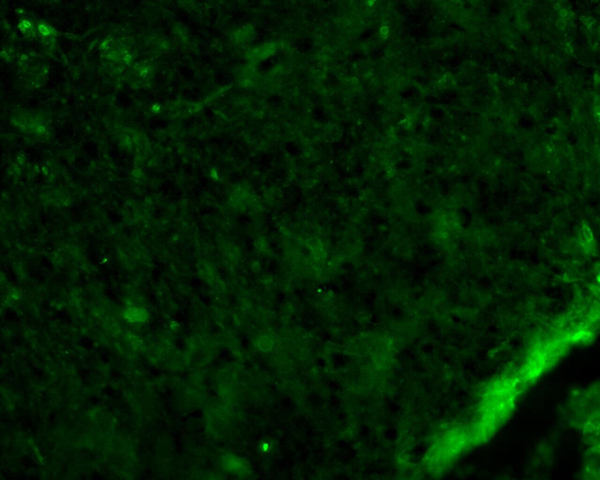

IHC (Immunohistochemistry)

(AAA327178 at 1/100 staining Human liver cancer tissue by IHC-P. The sample was formaldehyde fixed and a heat mediated antigen retrieval step in citrate buffer was performed. The sample was then blocked and incubated with the antibody for 1.5 hours at 22 degree C. An HRP conjugated goat anti-rabbit antibody was used as the secondary.)